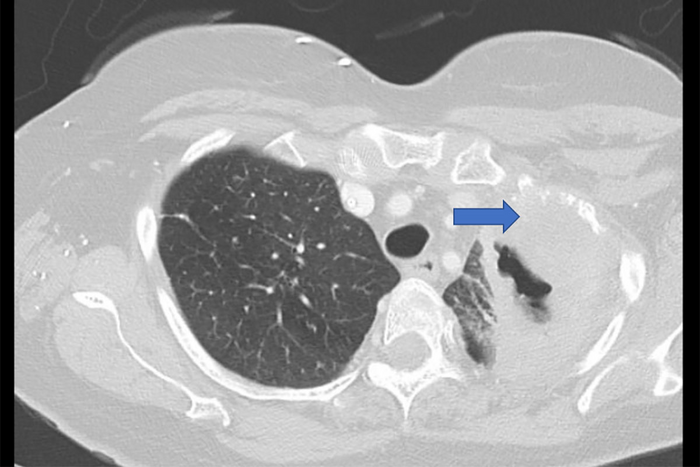

图:圣路易斯华盛顿大学医学院的一笔拨款将支持研究肺癌复发。图为计算机断层扫描(CT)显示肺肿瘤(蓝色箭头)。

图片来源:圣路易斯华盛顿大学医学院